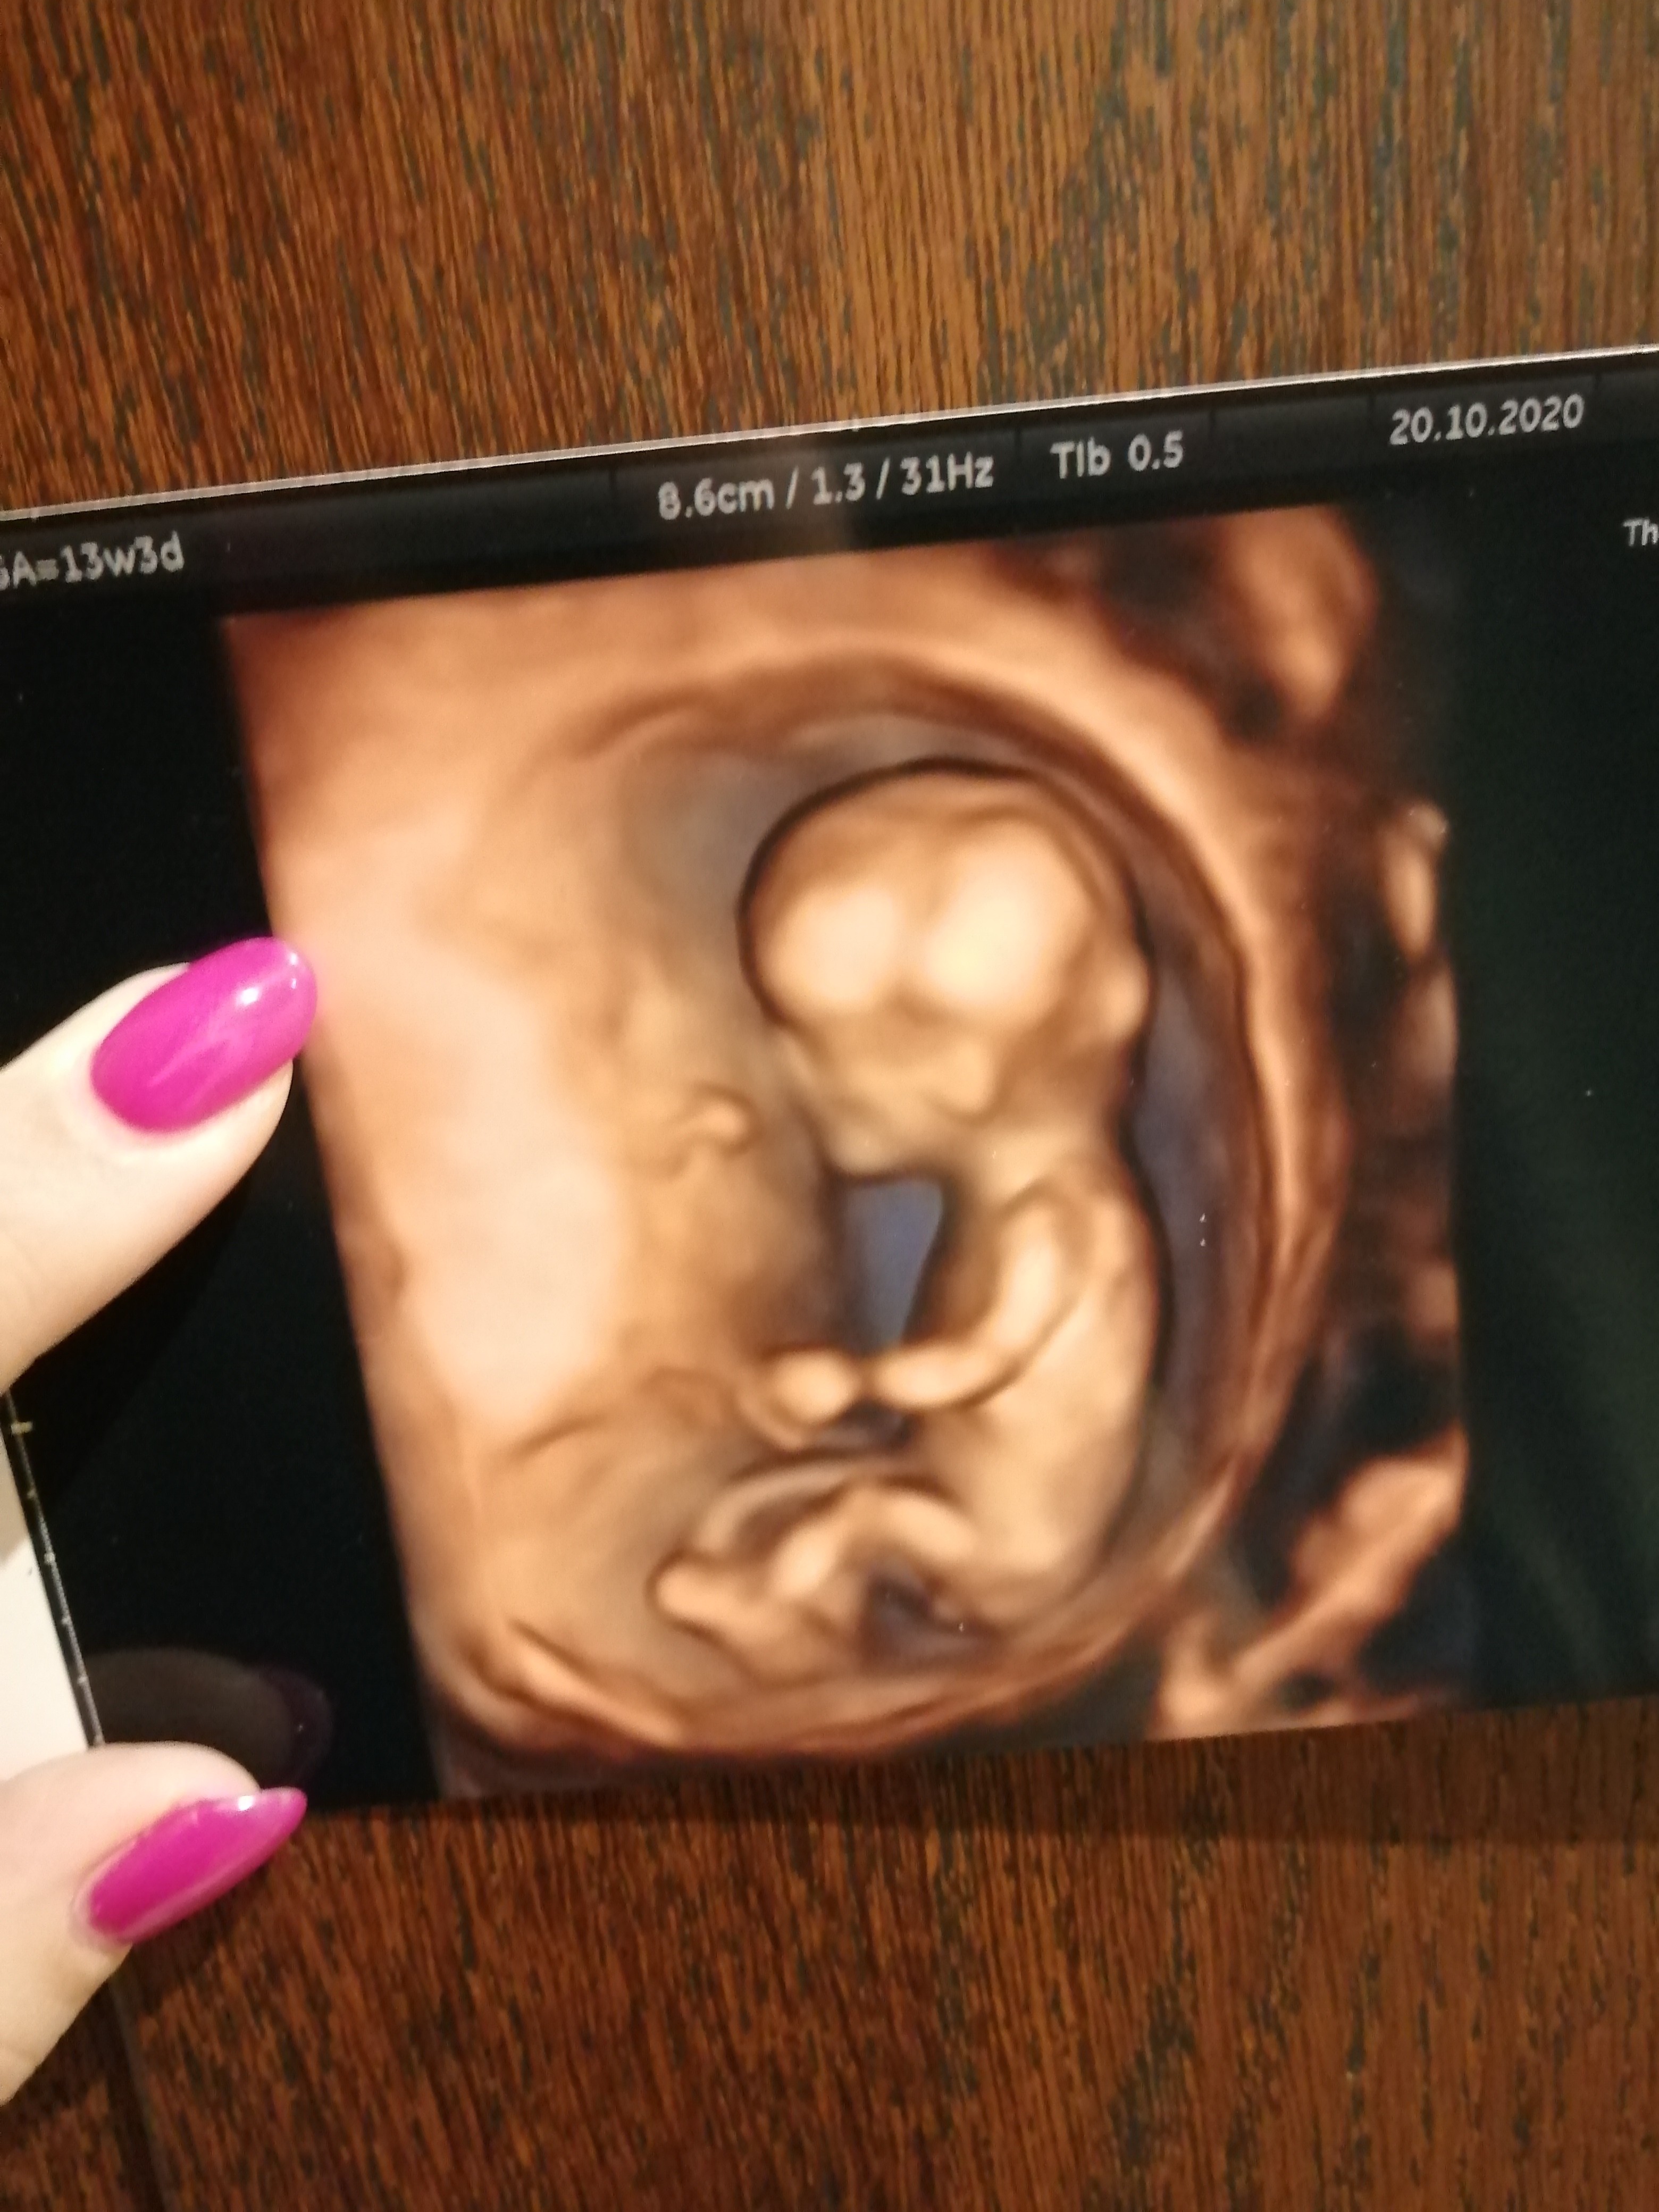

To bylo 2 tyg temu ale lekarz mowi ten dzis ze w 12 czy 13 narzady rodne wygladaja tak samo i ja juz sie na 3 chłopca po tym zdj nastawilam a tu moze bedzie jednak córcia

Załączniki

• IMG_20201020_201238.jpg

IMG_20201020_201238.jpg

1,4 MB · Wyświetleń: 102